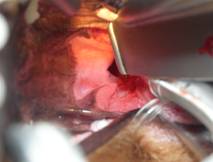

45-02

全身麻酔下にて異物除去を行う。

喉頭部は腫れ出血している。